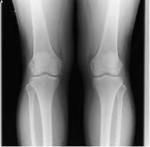

鵞足炎の特徴と原因

足首と股関節に挟まれた膝は中間関節と言い、足首や股関節の影響を受けやすい事が特徴と言えます。

膝の内側には骨盤と直接つながる3つの筋肉が存在します。

この3つの筋肉が原因とよく言われますが、この3つを硬くする根本原因を見つける事が必要です。